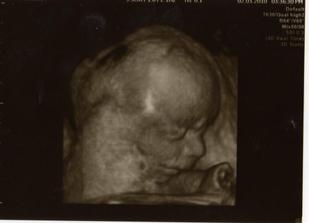

2.3.2010, 22+4tt - 3D UTZ